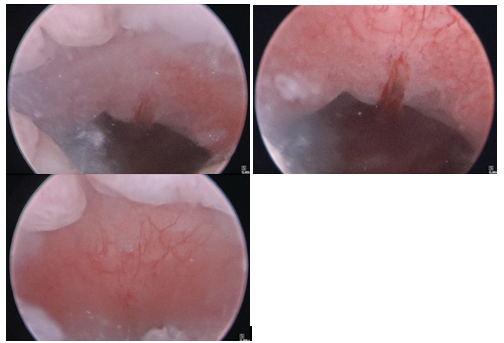

Hysteroscopy in the operating room revealed anterior CSD cephalad to the internal cervical os (Figure 5), an unremarkable uterine cavity, and bilateral ostia. Laparoscopy revealed dense adhesions of the bladder to the anterior lower uterine segment. The adhesions were lysed allowing for greater mobilization of the uterus. The CSD was excised and repaired. The post-operative period was uneventful, and the patient went home the same day.

Figure 5 Patient 2, Hysteroscopic images: Hysteroscopy showing anterior CSD cephalad to the internal cervical os, with an unremarkable uterine cavity.